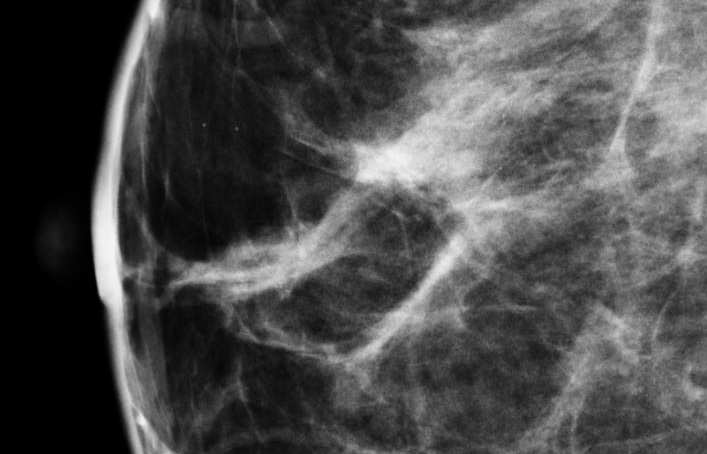

Breast density is the term used to describe the variation in dense tissue on a mammogram image. Fatty breast tissue appears more radiologically translucent than dense (fibroglandular) breast tissue. Regions of a breast that comprise fatty tissue will appear darker on a mammogram, while regions that comprise dense tissue appear whiter.

Increased breast density has been shown to mask cancers on the mammogram as well as to be associated with future risk of breast cancer. Recent legislation in several states mandates that women be given information about breast density in order to guide decisions about breast cancer screening.